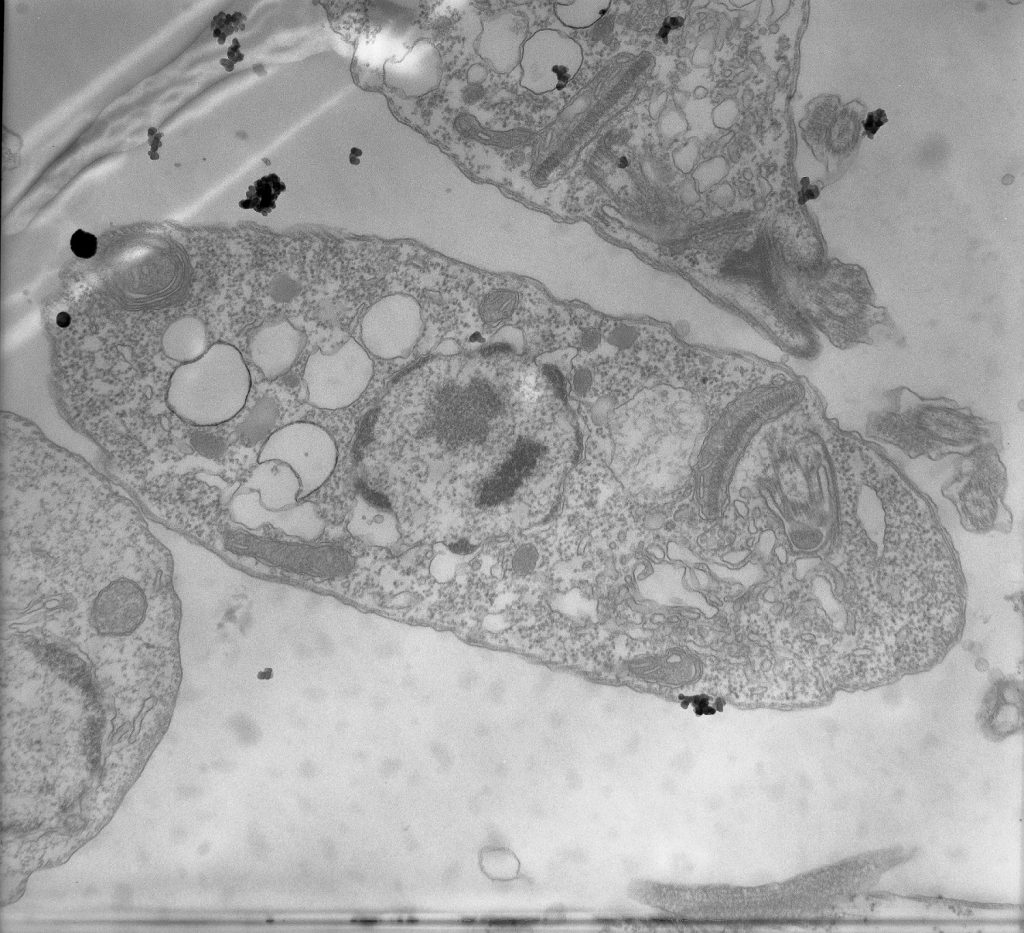

Parásito de Leishmania tratado con el compuesto RV122C (Cortesía: Alicia Ponte-Sucre)

Los autores del estudio emplearon dos enfoques para comprender la resistencia a los fármacos: uno que identifica las proteínas sobreexpresadas de forma exclusiva en cada aislado de L. donovani y otro centrado en las proteínas sobreexpresadas comúnmente en todos los aislados. En total, identificaron 1825 proteínas sobreexpresadas en el parásito. “Nuestros hallazgos revelan que cada aislado clínico resistente a los fármacos posee una huella proteómica única, pero comparte adaptaciones, particularmente en la reprogramación metabólica, la respuesta al estrés y la regulación de la expresión génica”.